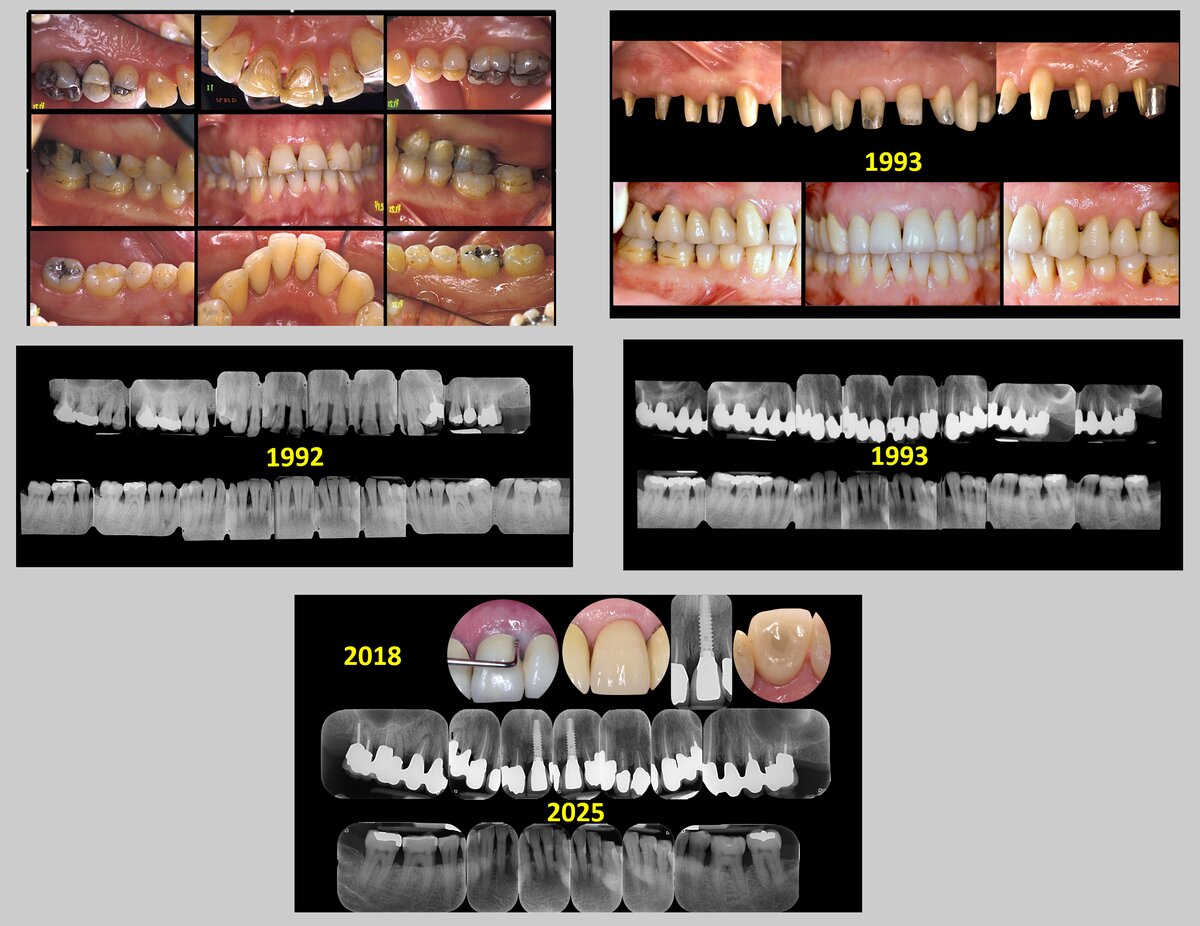

If the goal is to realize a prosthesis with optimal aesthetics, we should first define what we mean by “optimal aesthetics” because the aesthetic perception varies widely from country to country, from person to person, and also between patients and dentists (Tonetti et al, 2025). If we define optimal aesthetics as a smile that appears naturally beautiful and in harmony with the patient’s facial features—so that one should not perceive the difference between restored and natural teeth—we find that this task is extremely difficult to accomplish in patients who have lost five or more teeth and 70-80% of the remaining tooth support (Figure 1). Unfortunately, the only way to achieve “optimal aesthetics” is often to replace the lost tissues with artificial gums. But can this kind of aesthetics be defined as “optimal”?

The consequences of this approach, from both aesthetic and functional perspectives, are substantial. If the goals of periodontal therapy have been achieved (Sanz et al, 2020; Tomasi et al, 2022), the teeth can be orthodontically moved and intruded to compensate for the soft- and hard-tissue loss, and a natural-looking smile is easier to regain (Figure 3). From a functional point of view, the benefit of keeping virgin, and not crowned, teeth is even greater. In teeth that have lost more than 50 per cent of attachment, in order to avoid “black triangles” between the teeth, the prosthetic finishing margin must be located not at the cementoenamel junction but at the gingival margin level, i.e. at the apical third of the root.